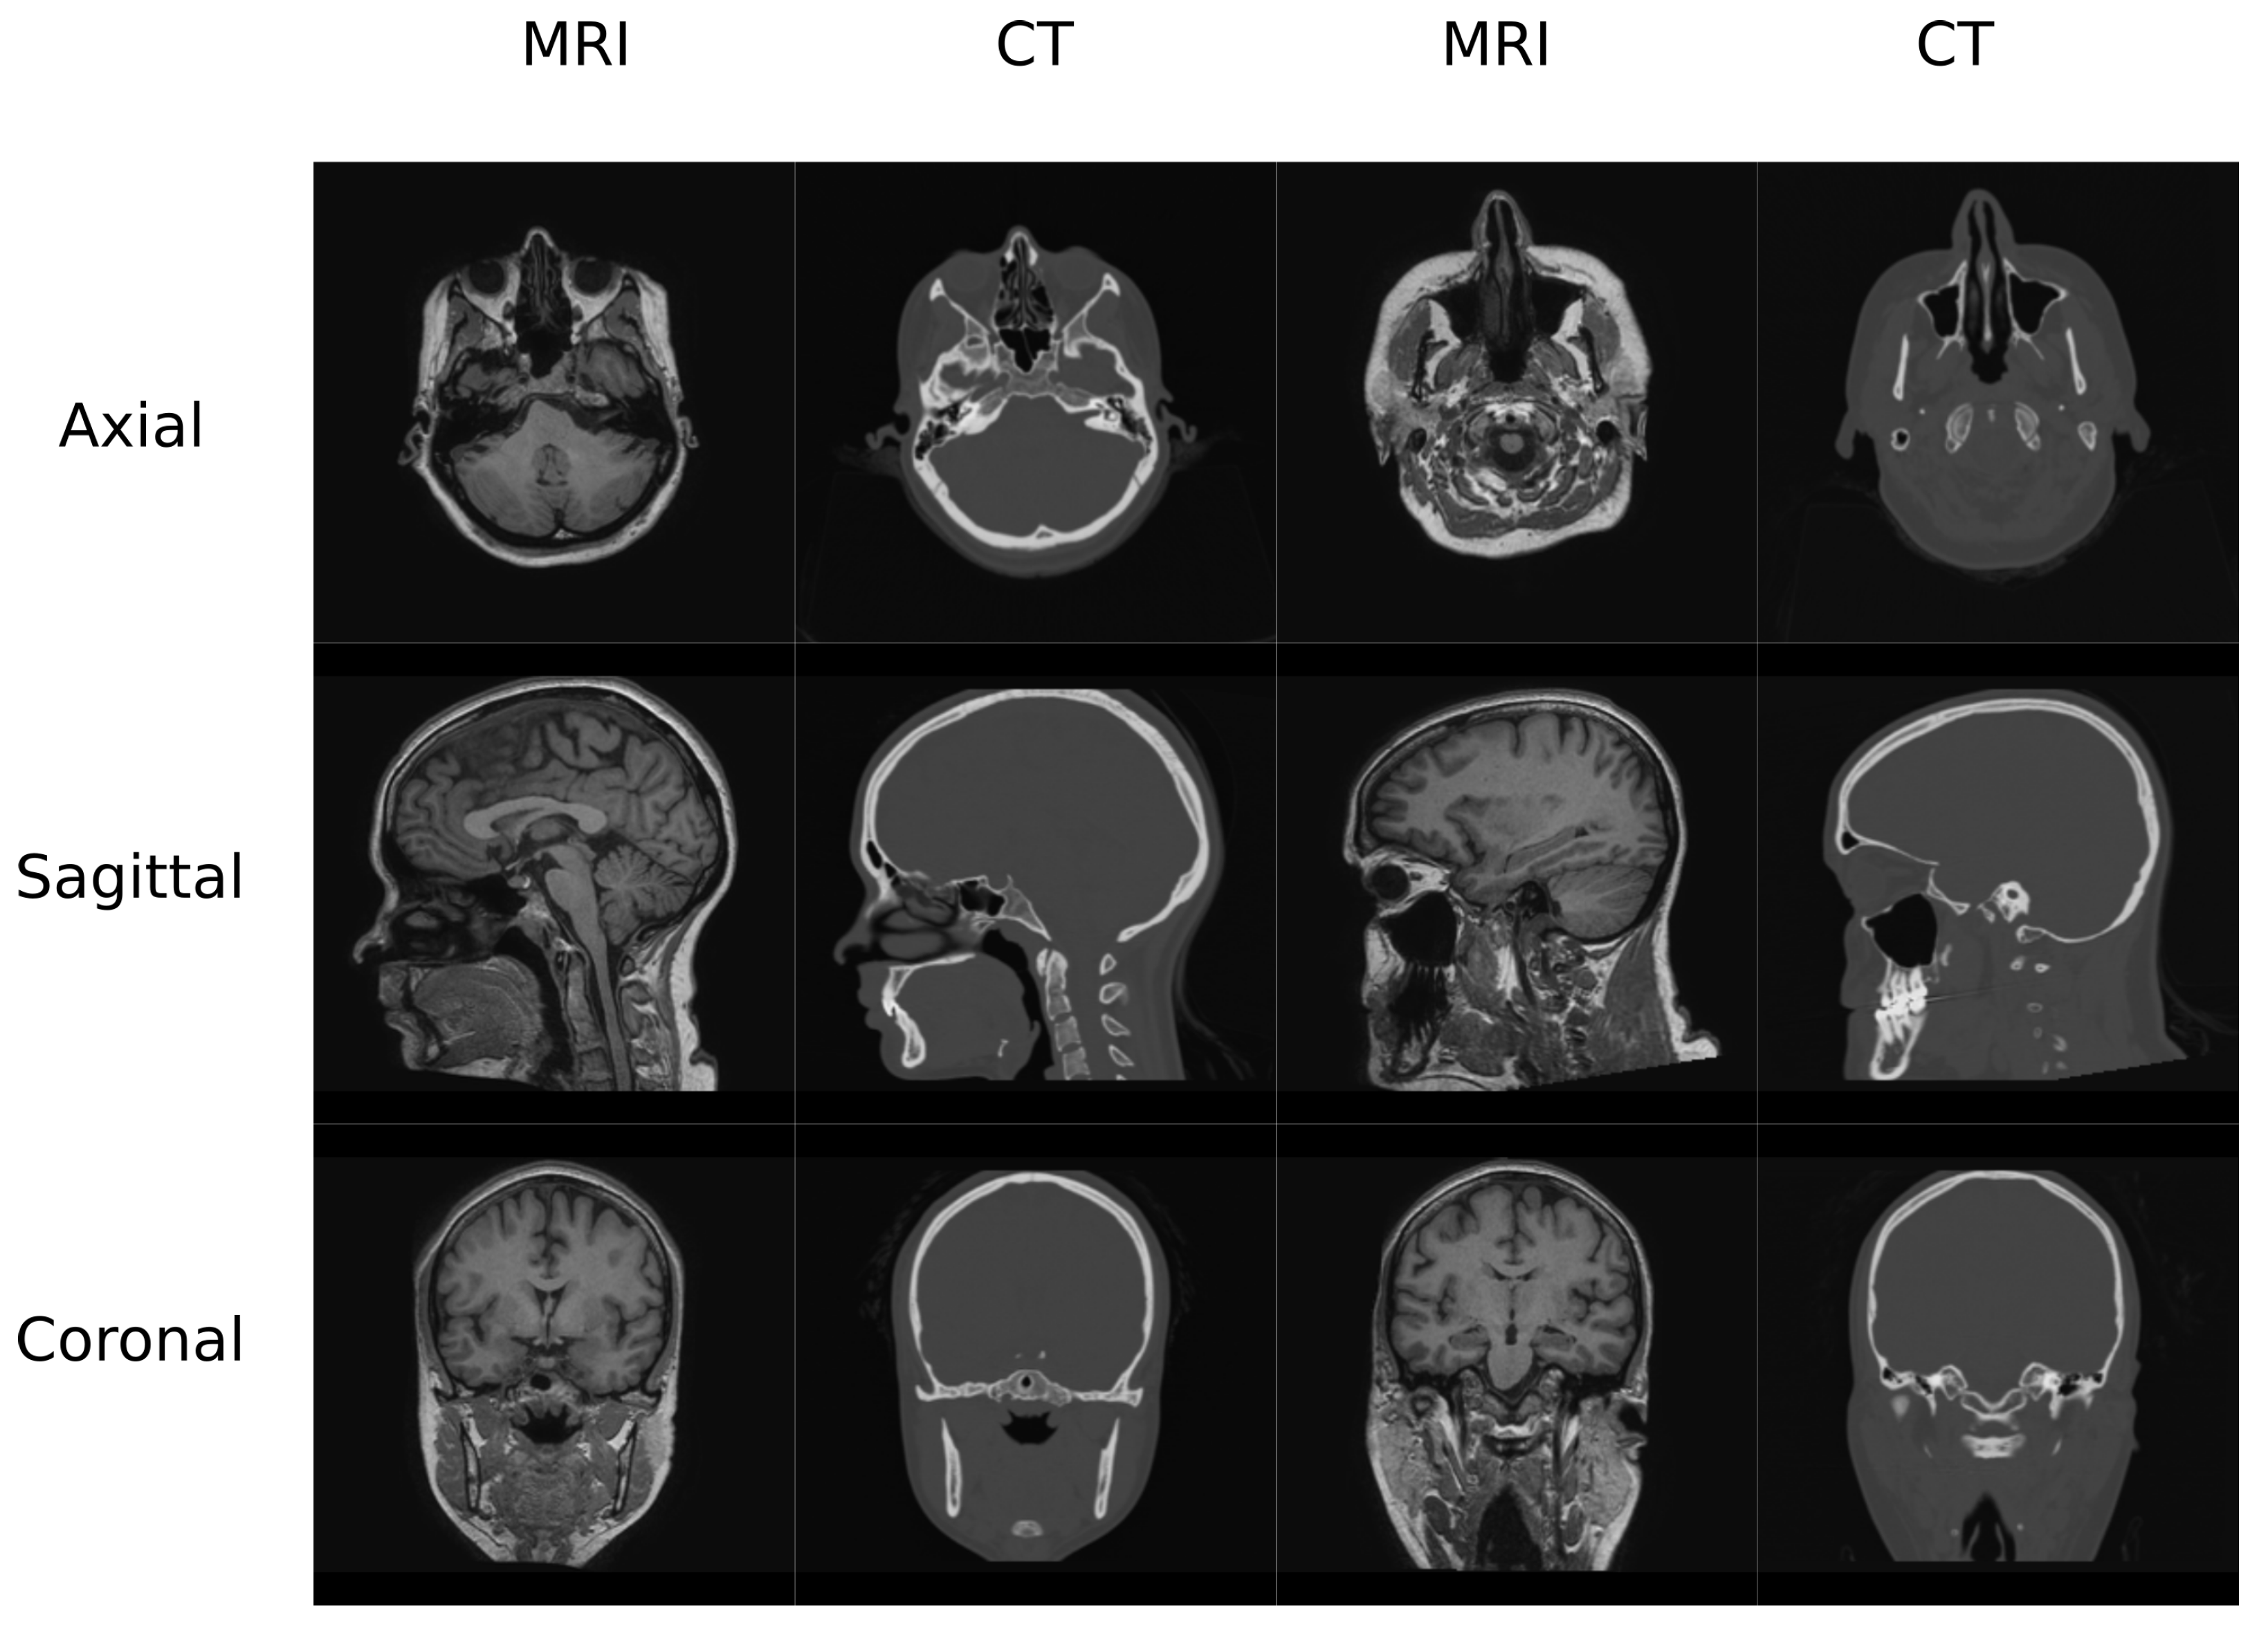

In this work, two datasets were used to train and test the different architectures that are reviewed. The first one (Figure 1) contained MR and CT head pairs from 19 healthy women (34.96 ± 5.23 y/o). MR images were acquired on a GE Signa HDxt 3.0-T MR scanner, and imaging was performed using a 3D T1-weighted sequence with a repetition time of 10.024 ms, echo time of 4.56 ms, inversion time of 600 ms, 1 excitation acquisition matrix of , isotropic 1 mm resolution, and a flip angle of 12°. Low-dose CT images were acquired on a Siemens Somatom Sensation 16 CT scanner with a matrix of , resolution of mm, slice thickness of 0.75 mm, pitch of 0.7 mm, acquisition angle of 0°, voltage of 120 kV, and radiation intensity of 200 mA.

Figure 1.

Head Data set example.

The second database (Figure 2) contained MR and CT images from the pelvis of 13 colorectal and 6 prostate cancer patients (61.42 ± 10.63 y/o, mean BMI 22.3 ± 2.88, 12 males/8 females). Additionally, images from follow-up visits for 9 of the colorectal cancer patients were also included in this study. MR and CT scans were performed on the same day with an average delay of 66 min. CT images were acquired on a Discovery PET/CT 710 scanner (GE Healthcare) with a matrix of , resolution of mm, slice thickness of 3.75 mm, pitch of 0.94 mm, acquisition angle of 0, voltage of 120 kV, and radiation intensity of 150 mA. MR data were acquired on a Biograph mMR scanner (Siemens Healthineers, Erlangen, Germany). The sequence was a dual echo Dixon-VIBE, which is the standard image for attenuation correction purposes. Dixon-Vibe acquisitions are composed by 4 sets of images: water, fat, in-phase and out-of-phase.

Figure 2.

Pelvis Data set example.